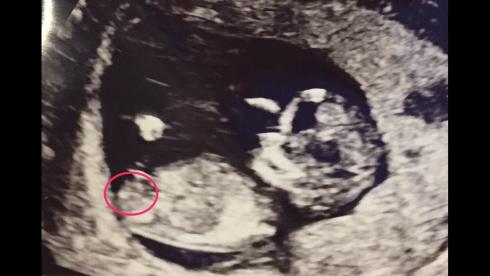

Hey any ideas whether this looks like a boy or girl? Scan at 12w1d, heartbeat was 168bpm. Nub/skull theories?Attachment 34670

I think boy. But best if you put the picture without the drawing, the circle is in the wrong place anyway :)